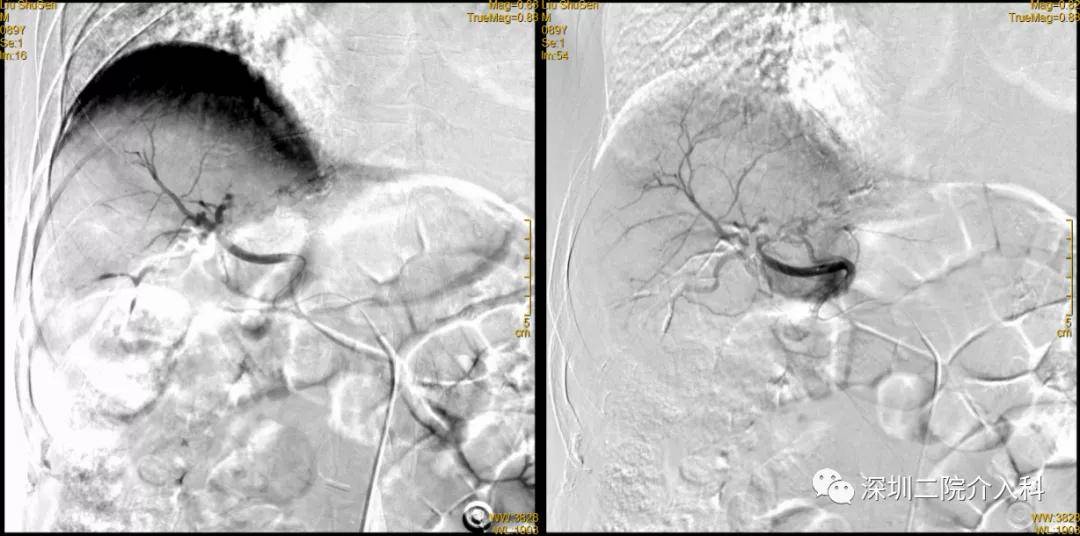

2020-12-15 术前MR增强

文章图片

2020-12-15 术前MR冠状位

治疗经过:2020-12-18 行TACE术

腹腔干造影

肝固有动脉造影

可见肝右叶明确肿瘤染色